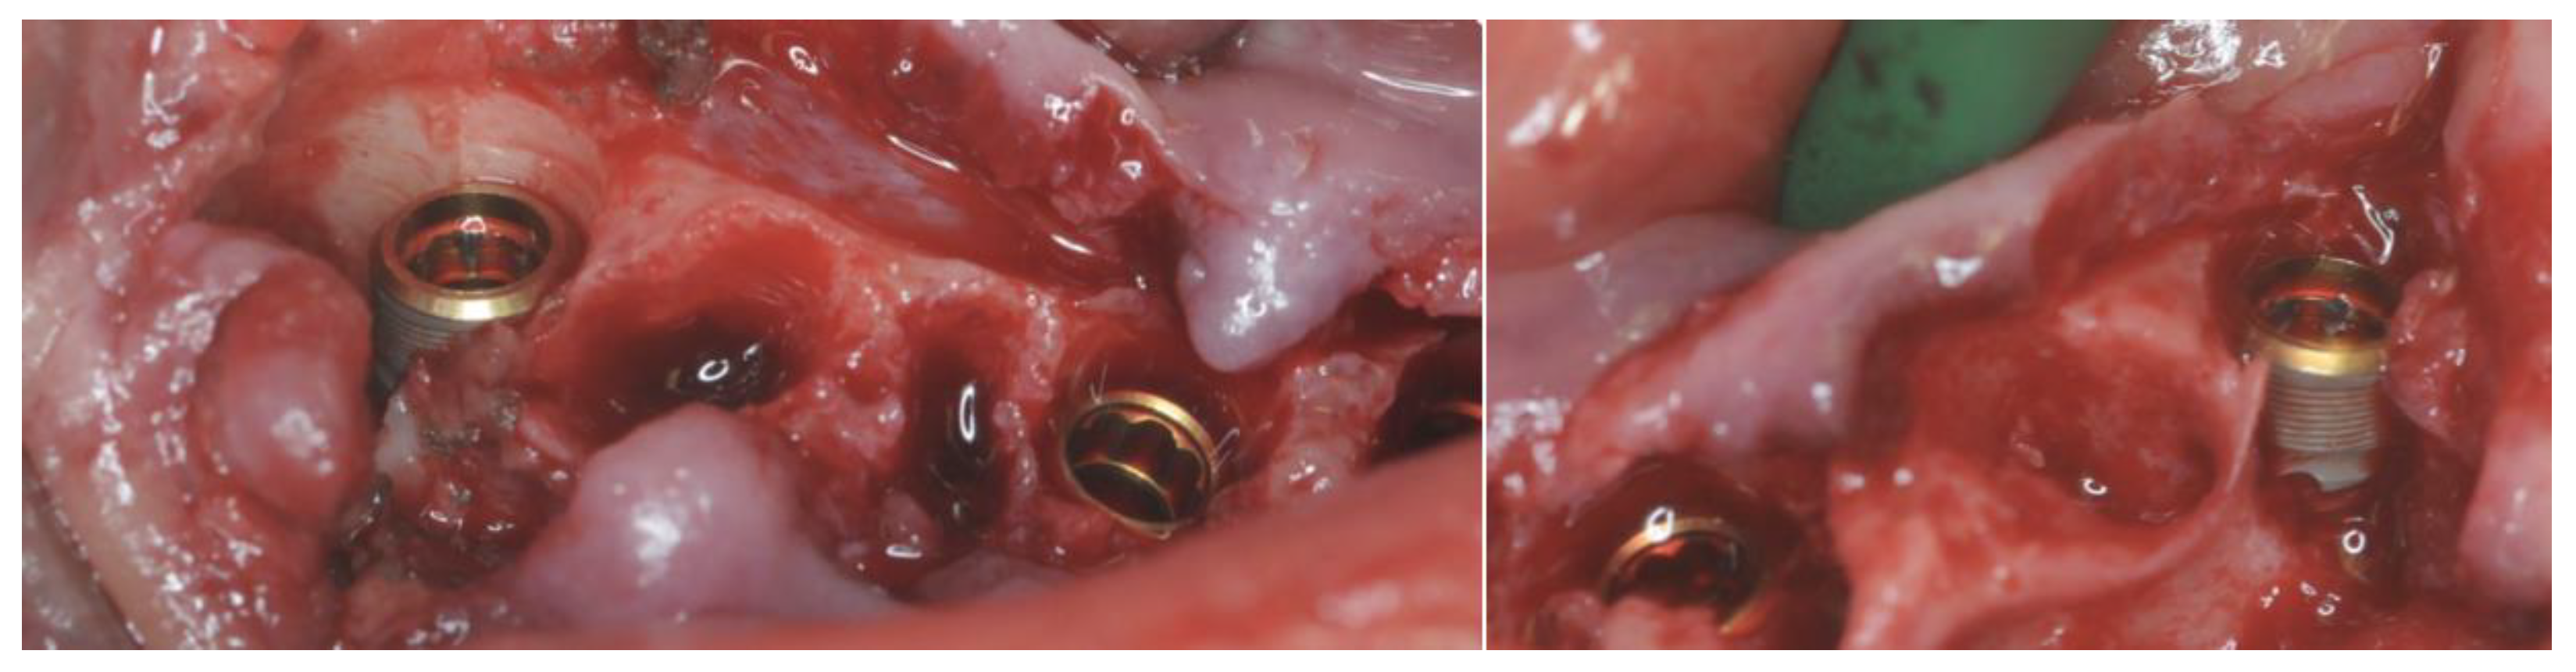

2.4. Surgery